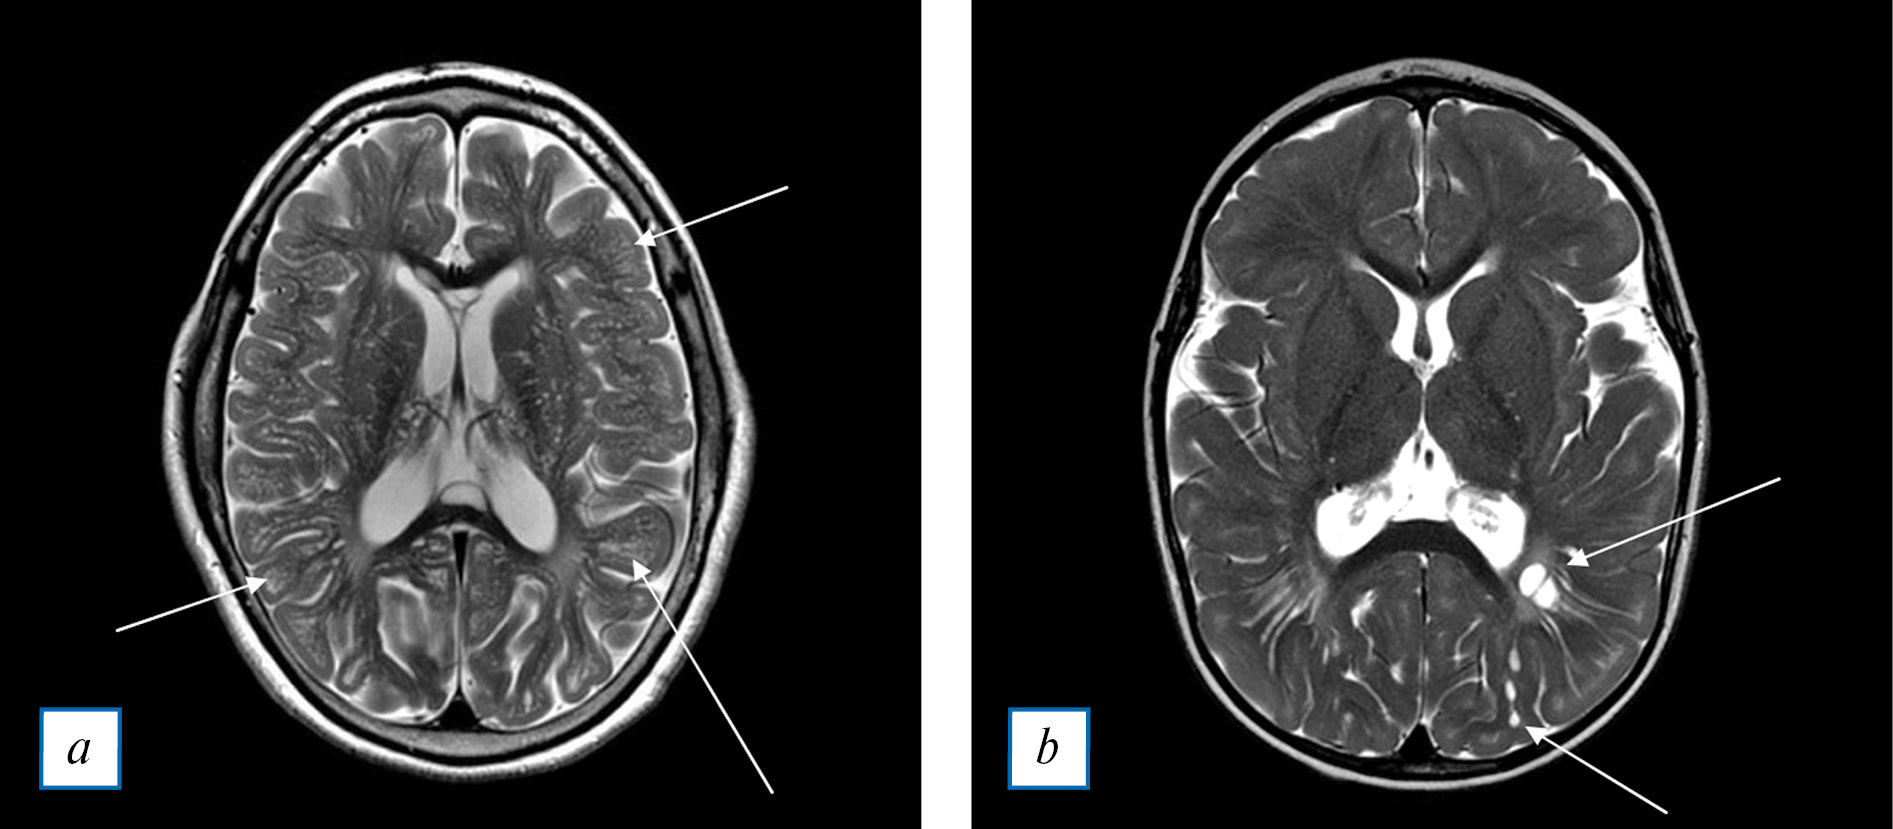

Термин «гидроцефалия» применяется при увеличении количества спинномозговой жидкости в ликворных пространствах головного мозга, что вызывает расширение желудочков мозга (вен-трикуломегалию) (рис. 2, а). Описано два механизма возникновения гидроцефалии у пациентов с МПС. Первый — отложение ГАГ в оболочках мозга, которое приводит к нарушению функций арахноидальных грануляций, снижая реабсорбцию спинномозговой жидкости. Для другого механизма существует гипотеза, что повышенная пролиферация костной ткани в области основания черепа и краниовертебрального перехода вызывает механическое затруднение венозного оттока от головного мозга [4, 8, 14]. Один или оба механизма вместе приводят к развитию сообщающейся (необструктивной) гидроцефалии, которая медленно прогрессирует, сопровождаясь дальнейшим расширением желудочков (обычно боковых и третьего) и субарахноидальных пространств. Результатом расширения ликворных пространств является формирование макроцефалии [14]. Как осложнение при гидроцефалии может выступать расширение подоболочечных пространств зрительных нервов. Если это состояние будет сохраняться длительное время, то может возникнуть атрофия зрительных нервов [14].

Вентрикуло-перитонеальное шунтирование (рис. 2, б) у пациентов с МПС при развитии гидроцефалии выполняется по индивидуальным показаниям, которые коррелируют с появлением симптомов внутричерепной гипертензии или ухудшением неврологического состояния.

Отдельно выделяют расширение большой затылочной цистерны (mega cisterna magna) (рис. 2, в), которое следует дифференцировать с арахноидальной кистой. Намного реже встречаются аномалия Киари 1-го типа и уменьшение размеров задней черепной ямки [17, 18].

Рис. 2. МРТ головного мозга: а (Т2-ВИ в аксиальной плоскости) — выраженное расширение боковых желудочков мозга как проявление гидроцефалии. Перивентрикулярное изменение белого вещества мозга следует дифференцировать между трансэпендимальным отеком и поражением белого вещества при мукополисахаридозе; b (Т2-ВИ в аксиальной плоскости) — прямыми стрелками показан шунт, расположенный в боковом желудочке. Изогнутая стрелка показывает расширенный и деформированный боковой желудочек. Следует отметить истончение перивен-трикулярного белого вещества мозга и расширение борозд мозга, что является проявлением атрофии; c (Т2-ВИ в сагиттальной плоскости) — стрелкой показано расширение большой затылочной цистерны (mega cisterna magna). Затылочная кость локально истончена, что обусловлено пульсацией ликвора.

Fig. 2. Head MRI: a (T2-WI axial plane) — lateral ventricles are markedly dilated due to hydrocephalus. Periventricular white matter lesions need to be differentiated between transependymal edema and cerebral lesions due to mucopolysaccharidosis; b (T2-WI axial plane) — arrow: shunt in a lateral ventricle; curved arrow: an enlarged and deformed lateral ventricle. Thinning periventricular white matter and enlarged cerebral sulci must be noted as a sign of cerebral atrophy; c (T2-WI sagittal plane) — arrow: an enlarged cisterna magna (mega cisterna magna). The occipital is bone locally thinned due to the liquor's pulsation.